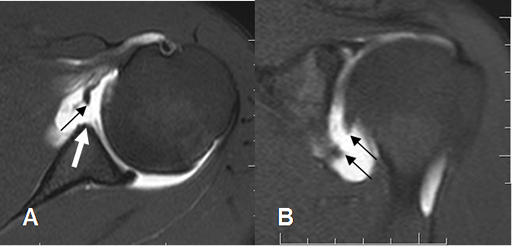

Fig 77 B. Ruptura del LGH medio.

A: ArtroRM axial en STIR. Lesión de Bankart (Flecha gruesa), en asocio con ruptura del LGHM. (Flecha delgada).

B: ArtroRM sagital en STIR. Ruptura del LGHM, con los extremos señalados con las flechas.